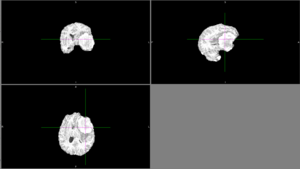

Sometimes, ANTs failed to remove parts of the skull close to the tumor or wrongly removed part of the brain.

Other times, ANTs extracted the brain well.